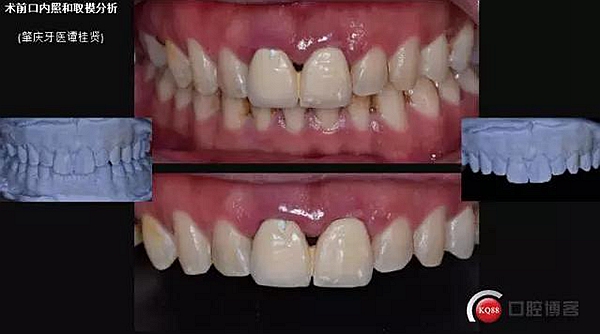

患者:32歲 男 要求重新修復(fù)前牙

主訴:上前牙咀嚼無力牙齦易出血,近日來烤瓷冠松動(dòng)脫落。

現(xiàn)病史:#11#21金屬烤瓷冠修復(fù)近十年了,近年來慢慢出現(xiàn)食物嵌塞不密貼,也非常影響美觀,但提起看牙醫(yī)便會(huì)驚出一身冷汗,近幾個(gè)月來牙冠慢慢出現(xiàn)松動(dòng),出現(xiàn)咬合痛,緊張的走進(jìn)了門診。

口內(nèi)檢查:很輕易就取下牙冠,均為殘冠殘根且繼發(fā)齲,#21尤為嚴(yán)重,已到齦下,牙周探診1.5mm,X線檢查:根尖陰影,欠充。

診斷:#11#21殘根,繼發(fā)齲,輕度牙周炎。

一診口內(nèi)照

口外照